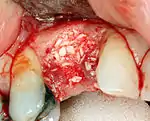

An incision is made across the area and the flap of gingiva is opened to show the bone of the jaw.

An incision is made across the gingiva, and the flap of tissue is reflected to show the bone of the jaw.

If bone width is inadequate it can be regrown using either artificial or cadaveric bone pieces to act as a scaffold for natural bone to grow around.